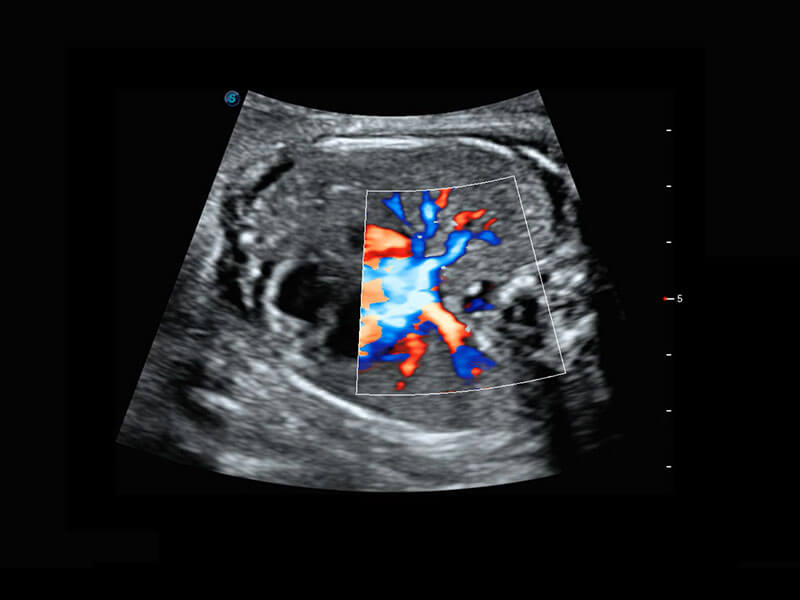

胎心筛查

P60搭载一系列胎儿心脏成像技术,实现精细的胎儿心脏评估。

• 四腔切面

• 四腔心血流

• 右室双出口

• 胎心容积成像